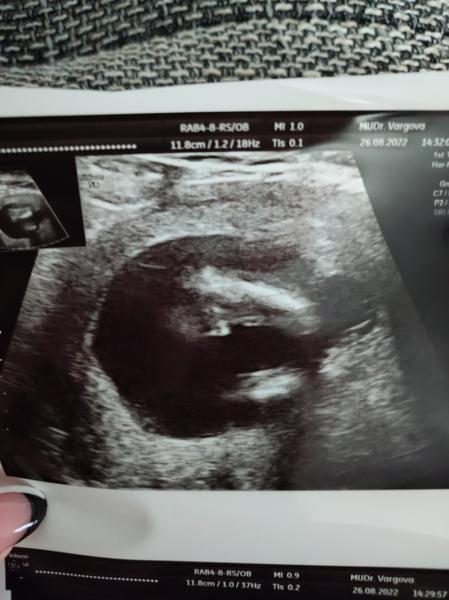

dnes 18tt hovorim ci sa nepozrie medzi nozky a ona ze zda.sa.ze.to vyzera.na babu.vravim ze fakt? Pred 2 tyzdnami ste vraveli ze ste.si na 90% ista.chlapcom a potom hladala a hladala a vravi ze sama nevie ze ona by povedala ze dievca ale ze.mozno toto je pindur (foto+ dalsie kde som znazornila nohy a cervenym to na co sa pytam) ze odspodu je tak vidno ritku a akoby sedelo v tureckom sede stehna a v strede cos male biele....

Z tejto fotky by som povedala, ze to stale moze byt jedno aj druhe...